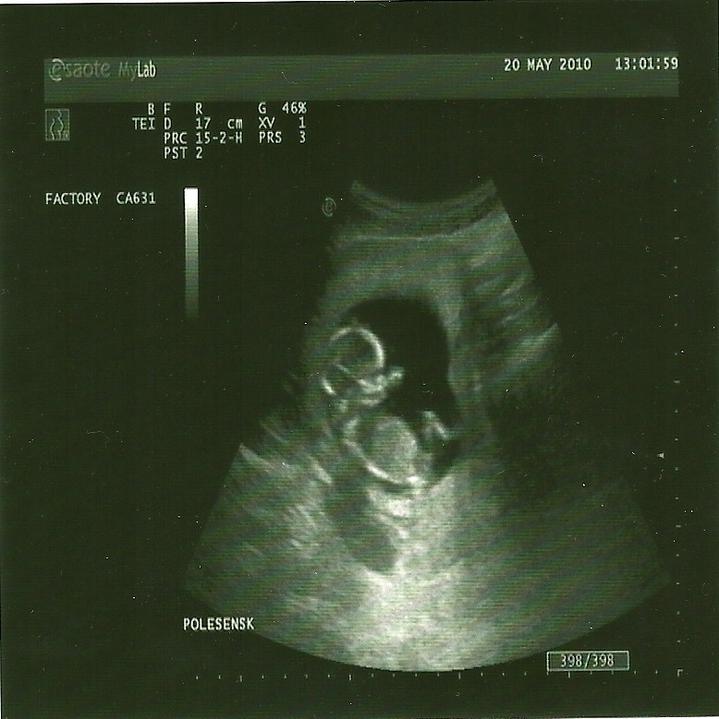

juchuu uz som doma.Super stuplik rastie ako z vody a aky je uz veliky:Daj rucicky,nozicky paraada :D zevraj bude mudry/a,lebo ma velku hlavku chichi :D:Daka som rada ze som ho zase videla 🙂

zajtra ideme na sono .... 🙂